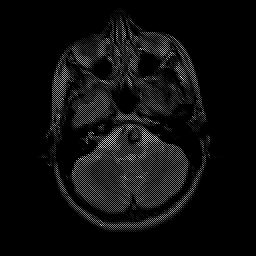

overlay -- Slice #5

[Home][Help][Clinical] Slice 5